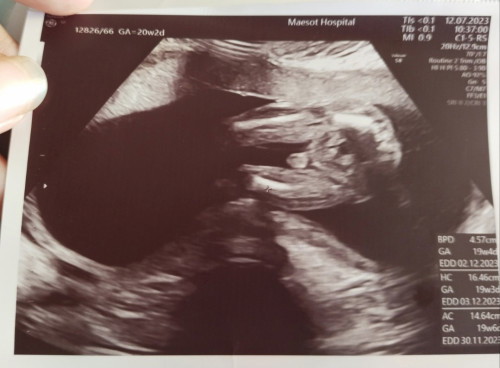

ไปซาวด์มาเมื่อวานค่ะคุณหมอบอกเป็นผู้ชาย...คุณแม่น่าจะผู้ชายเหมือนกันนะคะ

ชายแน่นอนแม่ ของเราเป็นแบบนี้เลย หมอบอกว่าน้องเปลี่ยนเพศไม่ได้แล้ว 555

อยากถามค่ะว่าน้องเป็นชายหรือหญิงค่ะพอดีไปซาวด์มาหมอไม่บอกค่ะ

น่าจะชาย นะคะ หนูไปซาววันนี้แบบนี้เหมือนกัน หมอบอก ชายค่ะ

ผู้ชายค่ะ มีจู๋ ถ้าเป็นผู้หญิงจะเห็นเป็นช่องว่างกลวงๆเลยค่ะ

โชลำมาเบยค่ะแม่น่าจะผช นะคะของเราก็เป็นแบบนี้หมอบอกผช.ค่ะ